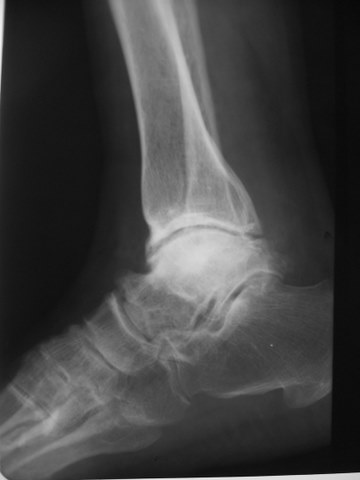

最近翻出一张刚上班时收藏的病例,男性,55岁,左踝部疼痛数年,加重2月余,正侧位片示:距骨塌陷变扁,密度增高,其内密度不均匀,关节面硬化毛糙,间隙变窄,跟骨短缩,诊断:踝关节改变符合大骨节病。

距骨塌陷变扁,密度增高,其内密度不均匀,关节面硬化毛糙,间隙变窄,考虑退行性骨关节病。

距骨扁,跟骨短,典型大骨节病。

大骨节病与别的骨关节病比较重要的区别是跟骨会有病变,但这个跟骨好像无异常,不太支持大骨节病,需流行病学支持。

这是我们这的地方病,很常见,西北地区,渭北,咸阳地区(永寿、麟游、礼泉等)都是高发区,跟骨外形变短,足弓略扁平,距骨改变是大骨节病成人型的典型表现,诊断上结合病人的居住史、饮水水质等不难做出诊断。